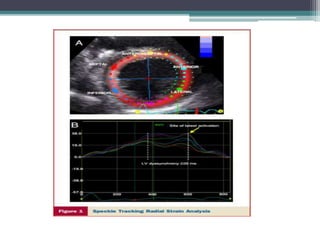

Intraventricular Radial Dyssynchrony,

John Gorcsan III et al ASE recommendation of echo for CRT 2008

Note that time to peak strain

in a normal subject occur

synchronously over a very

narrow time range.

Dyssynchrony is shown as

the difference in timing of

peak strain from earliest to

latest segment